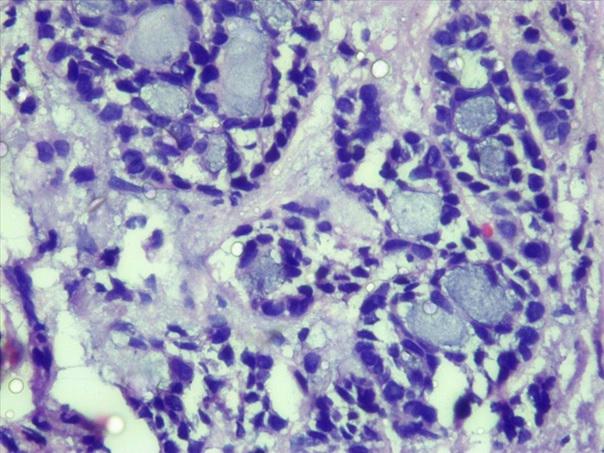

*Case 3 : Pr Modupeola Samaila/ Dr Rimamscep Ifusumu

email: mamak97@yahoo.com

Clinical detail: Female, 38 years. Orbital cystic tumour of 2 years duration.

Clinical diagnosis is orbital tumour query mucormycosis.

Please, consult the virtual slides of Case 3 below.